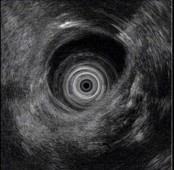

问题 男性,44岁反复上腹钝痛2年余伴纳差,超声内镜如图,胰腺病变可能的诊断是 ( )

选项 A.正常 B.胰腺囊肿 C.慢性胰腺炎 D.胰腺囊腺癌 E.胆总管结石伴扩张

答案 C